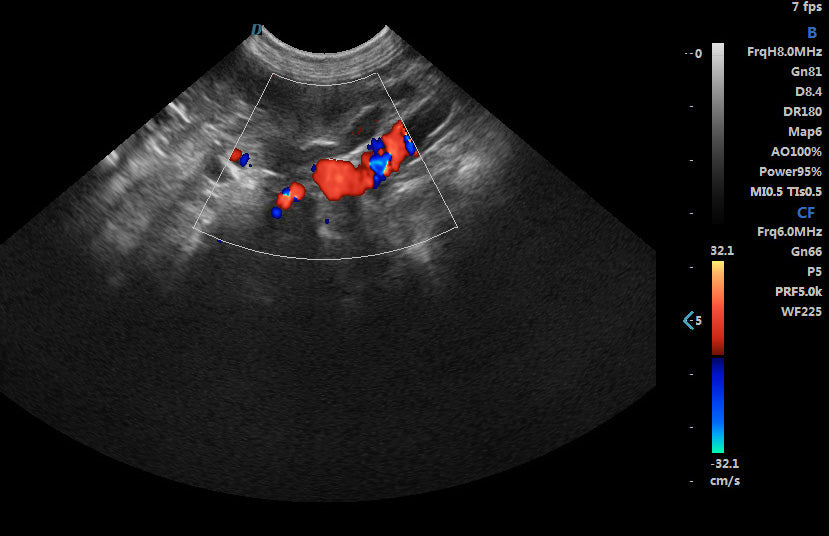

2. Excellent image processing functions, including spectral pulse Doppler, directional energy Doppler, spatial composite imaging, and tissue harmonic imaging technology.

Spectral Pulse Doppler

Directional Energy Doppler

Real-time Triplex